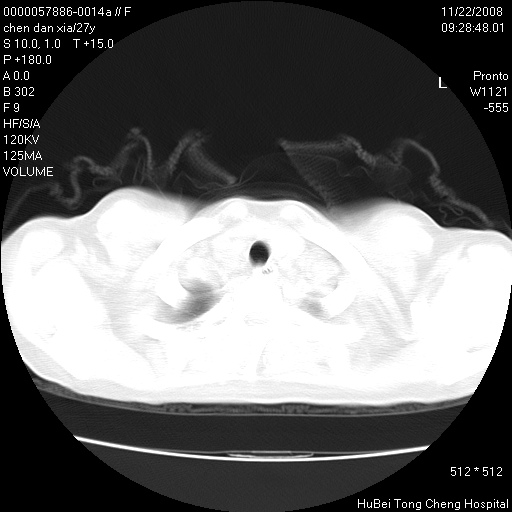

气管前腔静脉后淋巴结肿大 右肺门纹理模糊

淋巴结核?

右下肺见片絮状影,两肺野内分布不均的小结节影,结核并肺内播散可能性大,建议结合实验室检查 .

右下肺纹理模糊;纵隔可见肿大淋巴节;右心缘旁结节,边缘光滑,纵隔窗病变范围较肺窗明显小,首先考虑右下肺结核,不排外淋巴瘤

下肺结节,结节内钙化,肺门纵隔淋巴肿大 结核可能性大

气管前腔静脉后淋巴结肿大 右肺门纹理模糊[br]淋巴结核?

1)考虑两肺感染性病变。2)纵隔淋巴结肿大。

气管旁,两肺门可疑淋巴结肿大,建议ct增强.